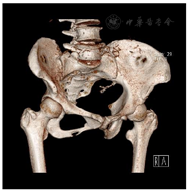

体格检查:体温36.5℃,心率90次/min,呼吸18次/min,血压130/90 mmHg(1 mmHg=0.133 kPa),心肺腹查体未见异常。专科检查:右髋部皮肤完好无破溃,无畸形及肿胀,肌肉无萎缩,骨盆无倾斜,双下肢基本等长;右侧腹股沟中点处压痛(+),叩痛(+),未触及肿块,髋关节周围轻度叩痛,下肢纵向叩击痛(±),右下肢皮温血运良好,足背动脉及胫后动脉搏动可触及;右髋关节屈曲、外展、外旋活动略受限,肌力Ⅳ级,膝关节、踝关节活动正常;右下肢直腿抬高试验及加强试验、大腿滚动试验、"4"字试验均阴性。血液化验结果无异常;骨盆CT重建结果示:右侧耻骨下支溶骨性骨质破坏,轻度膨胀,边缘清晰,未见骨膜反应(图1);髋部增强MRI结果示:右侧耻骨下支病变,考虑恶性肿瘤可能性大,骨转移瘤不除外(图2);全腹部CT、颅脑CT、肺部CT、胸腰椎MRI结果无异常;ECT示:右侧耻骨下支核素浓聚,考虑恶性肿瘤可能性大;胃肠镜结果回报:慢性非萎缩性胃炎。CT引导下病灶穿刺活检病理结果回报:送检物为纤维及骨组织,伴片状坏死,局部区域可见少量组织细胞样细胞、小淋巴细胞及少许嗜酸性粒细胞,结合免疫组化染色及影像学报告,考虑LCH。免疫组化结果:AE1/AE3(−),CD163(+),CD1a(+),Langerin(+),S-100(+),CD30(−)(图3)。

患者病变在右侧耻骨下支,首发症状为骨痛伴有髋关节活动受限。影像学提示右侧耻骨下支溶骨性骨质破坏,轻度膨胀,边缘清晰,未见骨膜反应。病灶穿刺活检可支持单灶性耻骨下支LCH的诊断。